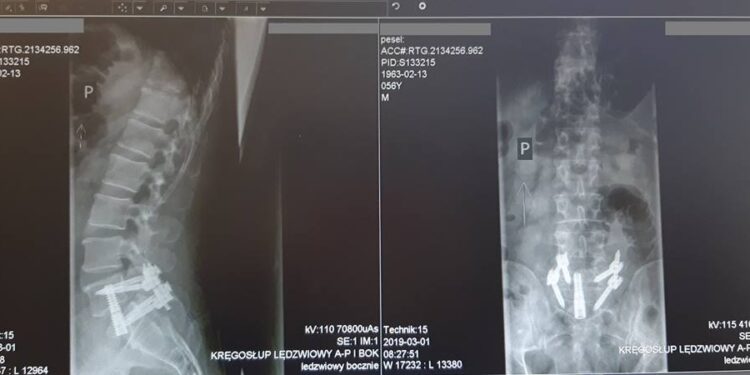

Neurochirurdzy z Gorzowa zastosowali nową technikę leczenia operacyjnego choroby zwyrodnieniowej kręgosłupa – pochwalił się na swoim Facebooku gorzowski szpital. Lecznica informuje, że to jedne z pierwszych tego typu zabiegów w Polsce. W gorzowskim szpitalu pięciu pacjentom wykonał je dr Piotr Kowalski z Oddziału Neurochirurgii.

– Niewątpliwą zaletą zastosowania metody z wykorzystaniem śrub osiowych Axialif 1L jest czas trwania operacji. Doświadczonemu chirurgowi samo wprowadzenie śruby osiowej zajmuje ok. 15 minut. Cała operacja trwa nie dłużej niż godzinę, czyli o połowę krócej niż np wykonywana metodą Alif z dojścia zaotrzewnowego przedniego przez brzuch. Jest też bardziej bezpieczna od tradycyjnej, podczas której odsłania się duże naczynia krwionośne (żyły, tętnice biodrowe, aortę, czy żyłę główną dolną) – czytamy w komunikacie lecznicy.